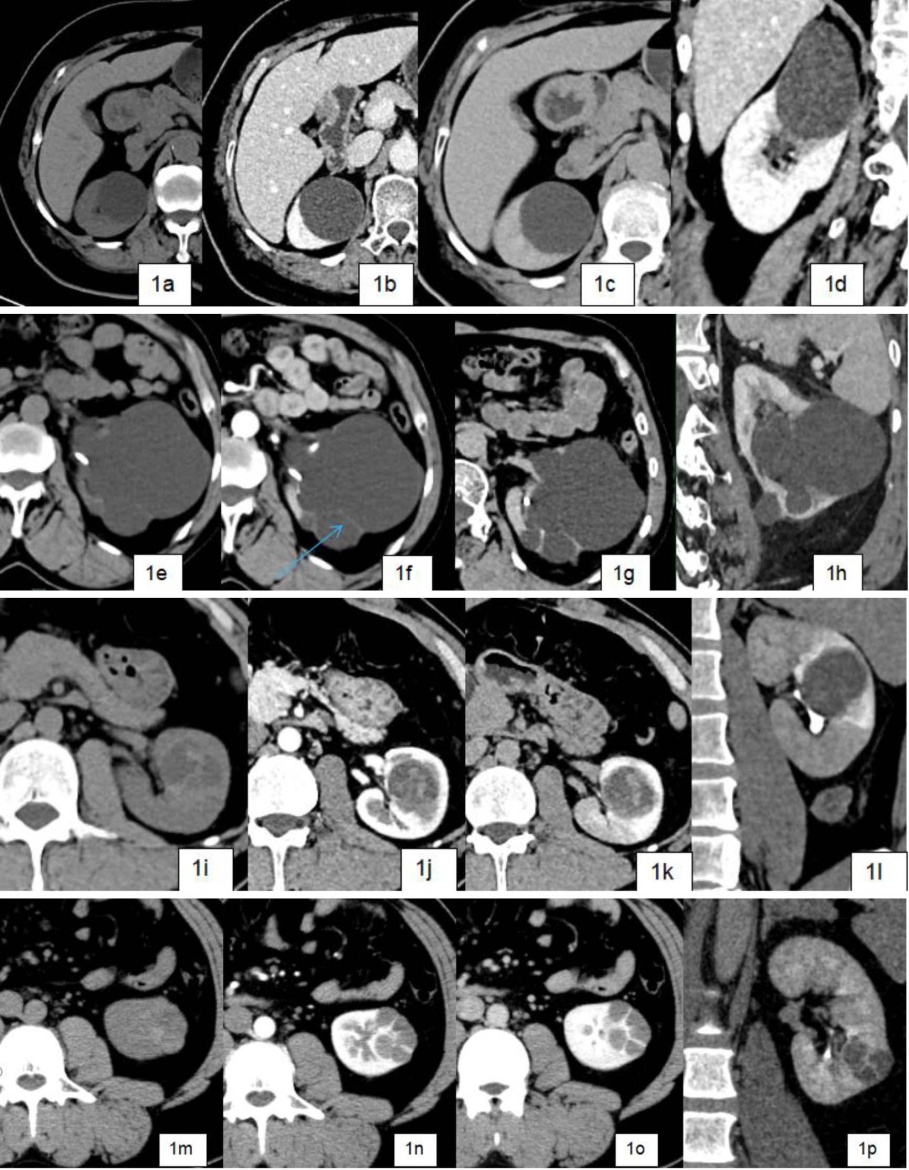

本研究旨在探讨肾囊性病变的影像学特征及其在良恶性鉴别中的临床应用,特别是基于Bosniak分级系统(2019版)对CT、MRI及超声造影(CEUS)技术的诊断标准与局限性进行系统分析。随着影像学技术的不断进步,肾脏囊性病变的检出率显著提高,然而,如何准确鉴别其良恶性仍然是放射科和泌尿外科面临的核心挑战。研究表明,恶性病变的核心影像特征包括厚壁(≥4 mm)、不规则分隔、壁结节强化及囊液浑浊度改变,而良性病变则多表现为薄壁(≤2 mm)、无强化分隔及均匀囊液(图1)。

Figure 1. Comparative example of imaging of renal cystic lesions and Bosniak grading

1. 肾囊性病变影像与Bosniak分级对照实例

图1(a)~(d)右肾囊性占位,壁薄(<2 mm)、光滑、无分隔、钙化,无实性成分,囊腔内密度均匀,近水样密度,增强后未见强化,病理结果单纯囊肿,Bosnikak I级;

图1(e)~(h)左肾囊性占位,壁薄,可见纤细分隔,内侧缘局部囊壁钙化,边界清,囊腔内密度均匀,近水样密度,增强后囊腔内未见明显强化,病理结果囊肿,Bosnikak II级;

图1(i)~ 1(l)左肾囊实性占位,内密度不均匀,可见实性成分及局部少许出血,壁毛糙、不均匀,增强后局部可见强化,考虑恶性倾向,病理结果,囊肿伴出血、局部囊壁乳头状瘤Bosnikak III级;

图1(m)~(p)左肾囊实性占位,内密度不均匀,可见实性成分,多发分隔,分隔 > 4 mm,边界不清,外侧壁可见结节状凸起,影像考虑囊性肾癌,病理结构为恶性;Bosnikak IVI级。